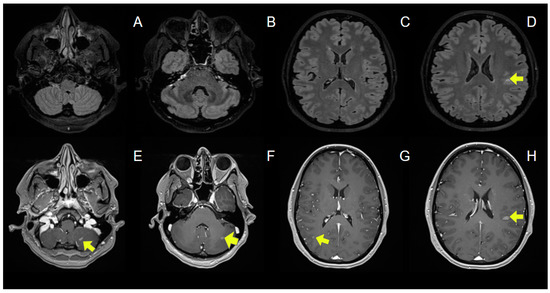

| Sterpi AE, et al. (2024) | 37/F | Breast Cancer | No | No | OLP, PLB, TRP, BVZ, LTR | IMRT | 30 | 10 | 2 months | Ataxia | Normal | No | Negative | Negative | Periventricular WM, corpus callosum, brainstem, cerebellum | - | IVMP with gradual tapering | Yes | No (6 months) | No new lesions (6 months) | N/A |

| Wong OY, et al. (2019) [31] | 31/F | Pituitary Macroadenoma | No | N/A | CBR | IMRT | 50.4 | 28 | 4 months | Decreased visual acuity, diplopia, facial numbness, tongue hemianesthesia | Normal | No | N/A | N/A | Subcortical WM, periventricular WM, brainstem, cerebellum | N/A | PSL | Yes | No (12 months) | No new lesions (12 months) | N/A |

| Borges A, et al. (2021) [26] | 28/M | Suprasellar Germinoma | No | No | CRB, ETP, IFS | WVRT | 24 | 15 | 4 months | Subjective cognitive impairment | Normal | Yes | Negative | Negative | Periventricular WM, subcortical WM, brainstem, cerebellum | + | No | Yes | No (12 months) | No new lesions (10 months) | N/A |

| Kemp S, et al. (2016) [29] | 65/F | Trigeminal Neuralgia | N/A | N/A | GBP | SRS | 90 | 1 | 3 months | Facial numbness, hemiparaesthesia, ataxia | Normal | Yes | N/A | N/A | TREZ | + | IVMP | Yes | Yes (10 months—left lower limb weakness, gait ataxia) | Periventricular WM, cervical spinal cord (10 months) | Fingolimod |

| Guillemin F, et al. (2020) [28] | 36/F | Pituitary Macroadenoma | No | N/A | N/A | SRS | 50.4 | 28 | 3 months | Dizziness, ataxia, nystagmus, left arm hypoesthesia | Normal | Yes | Negative | Negative | Brainstem, cerebellum, subcortical WM | + | IVMP | Yes | Yes (6 months—weakness Nystagmus) | Infratentorial lesions (6 months) | Beta-1A- Interferon |

| Esakia T, et al. (2021) [27] | 34/M | Nasophary-ngeal Carcinoma | No | N/A | CSP, 5FU | Focal RT | 66 | 33 | 2 months | Headache, ataxia, nystagmus | N/A | N/A | N/A | N/A | Cerebellum, periventricular WM | + | IVDEX with gradual tapering | Yes | No (24 months) | No new lesions (24 months) | N/A |

| Toljan K, et al. (2021) [30] | 41/M | Pituitary Macroade- noma | No | No | N/A | IMRT | 50.4 | 28 | 3 months | Diplopia, facial hemihypoesthesia, dysarthria, tongue numbness, ataxia, hemiparesis, single-sided hypoacusia | 13 cells/μL Protein: 50 mg/dL | No | Negative | Negative | Brainstem, cerebellum | + | IVMP followed by DEX | Yes | No (11 months) | No new lesions (11 months) | N/A |